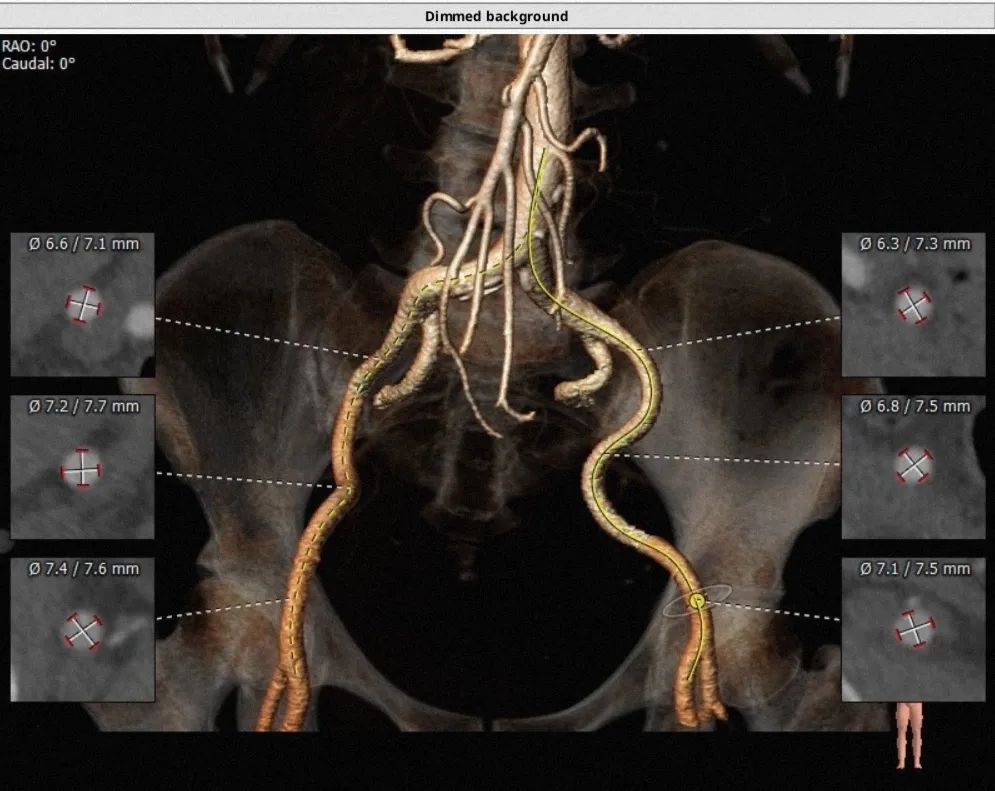

通过FEops报告选型

瓣环平面相关:

面积为406.4mm2

周长为74.2mm

周长导出径为23.6mm

面积导出径为22.7mm

平均径为22.7mm

CT评估

瓣环直径:24.5mm,左室流出道直径:26.9mm

主动脉窦:27.3*30.2*32.1mm,STJ:27.2mm

升主动脉直径:31.2,心脏夹角:59度